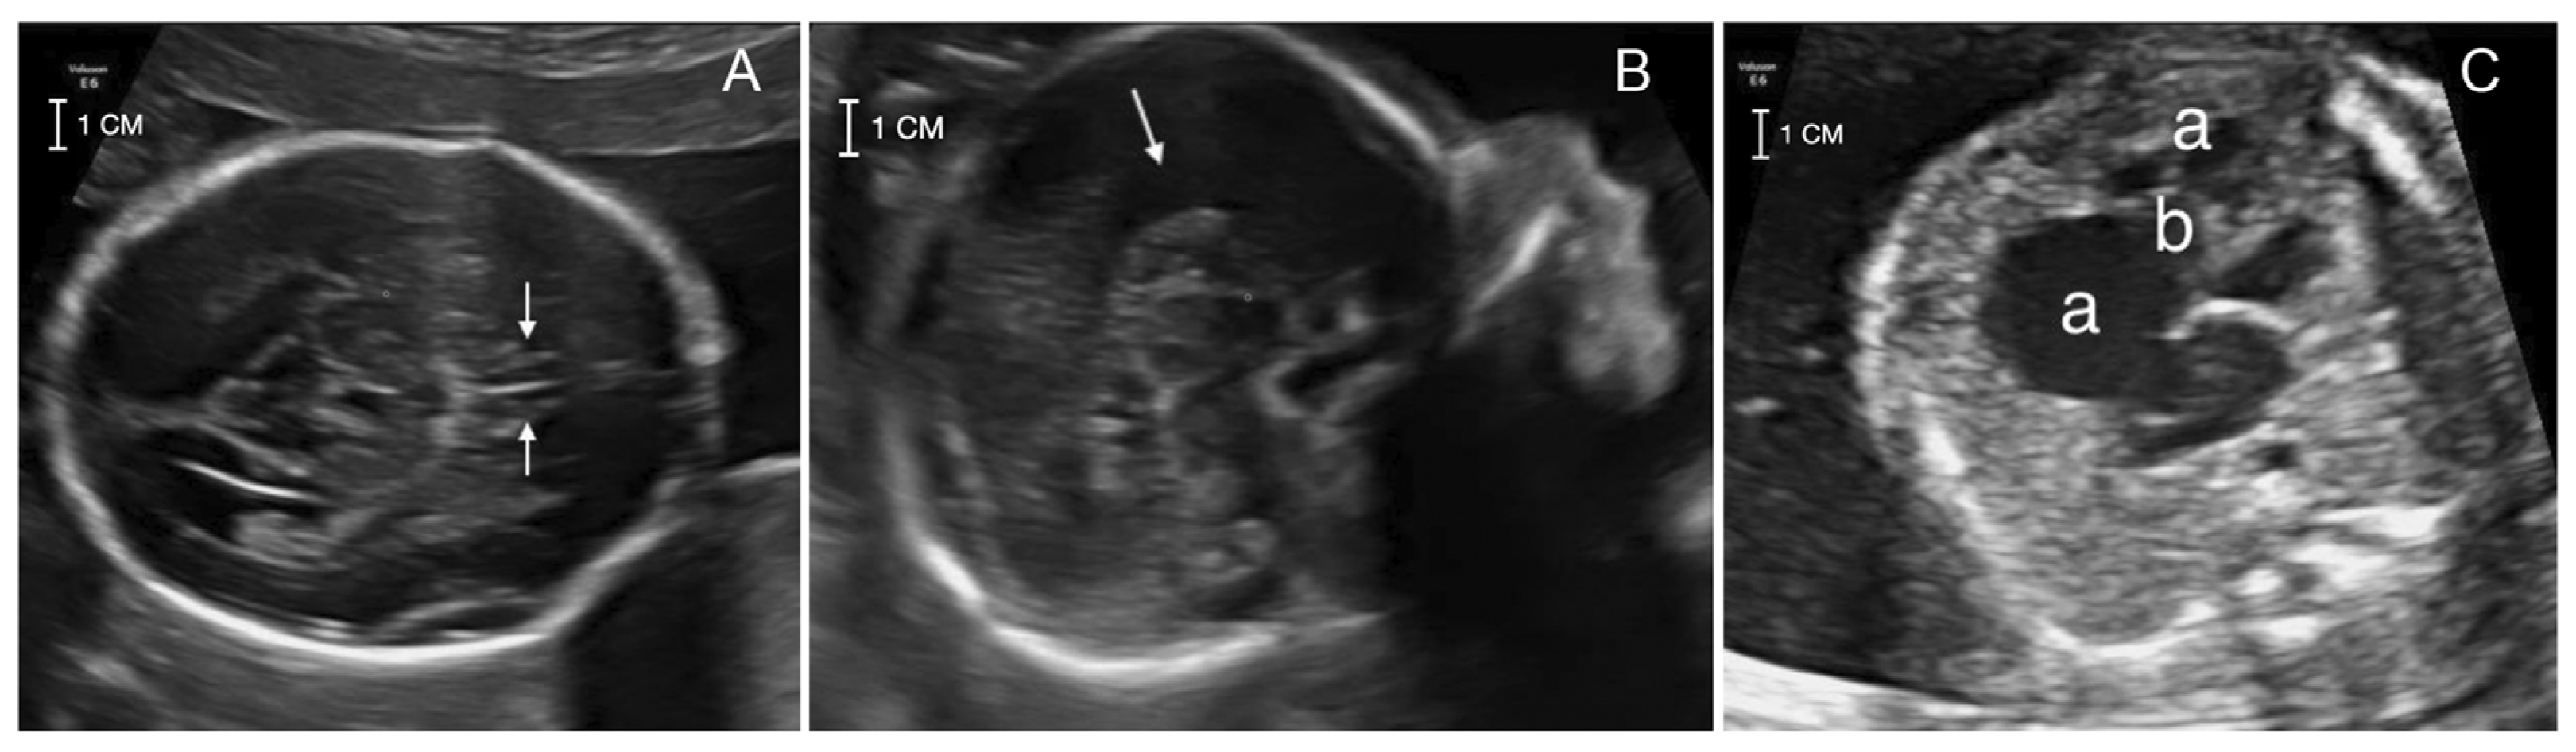

A 41-year-old pregnant woman was referred at 22 weeks of gestation for genetic counseling due to an abnormal ultrasound with suspected corpus callosum agenesis and heart defect. The family history was unremarkable for chromosomal abnormalities, congenital anomalies, metabolic disorders or drug exposure before pregnancy. The couple has a healthy son of 7 months of age and a healthy daughter from a previous relationship. The first trimester screening for trisomies 21, 18 and 13 turned out at low risk and ultrasound screening at 13 + 2 weeks was unremarkable. The II trimester ultrasound screening (21 + 2) did not detect the cavum of septum pellucidum and suspected an atrial-ventricular canal defect. Two II level fetal ultrasonographies performed at 21 + 2 and 22 + 1 weeks and a fetal MRI performed at 21 + 4 weeks confirmed the absence of septum pellucidum and pericallosal artery with complete corpus callosum agenesis. Heart evaluation revealed cardiomegaly with wall hypertrophy and disproportion with a prevalence of the right heart chambers, wide tricuspid insufficiency and downward displacement of septal leaflet, suspecting Ebstein’s anomaly (Figure 1).

Figure 1. The II level ultrasound screening at 22 + 1 showing: (A) the absence of cavum of septum pellucidum (white arrows); (B) the corpus callosum agenesis (white arrow); (C) the heart anomaly with the prevalence of the right heart chambers (a) and displacement of the tricuspid valve structure (b), consistent with Ebstein’s anomaly.